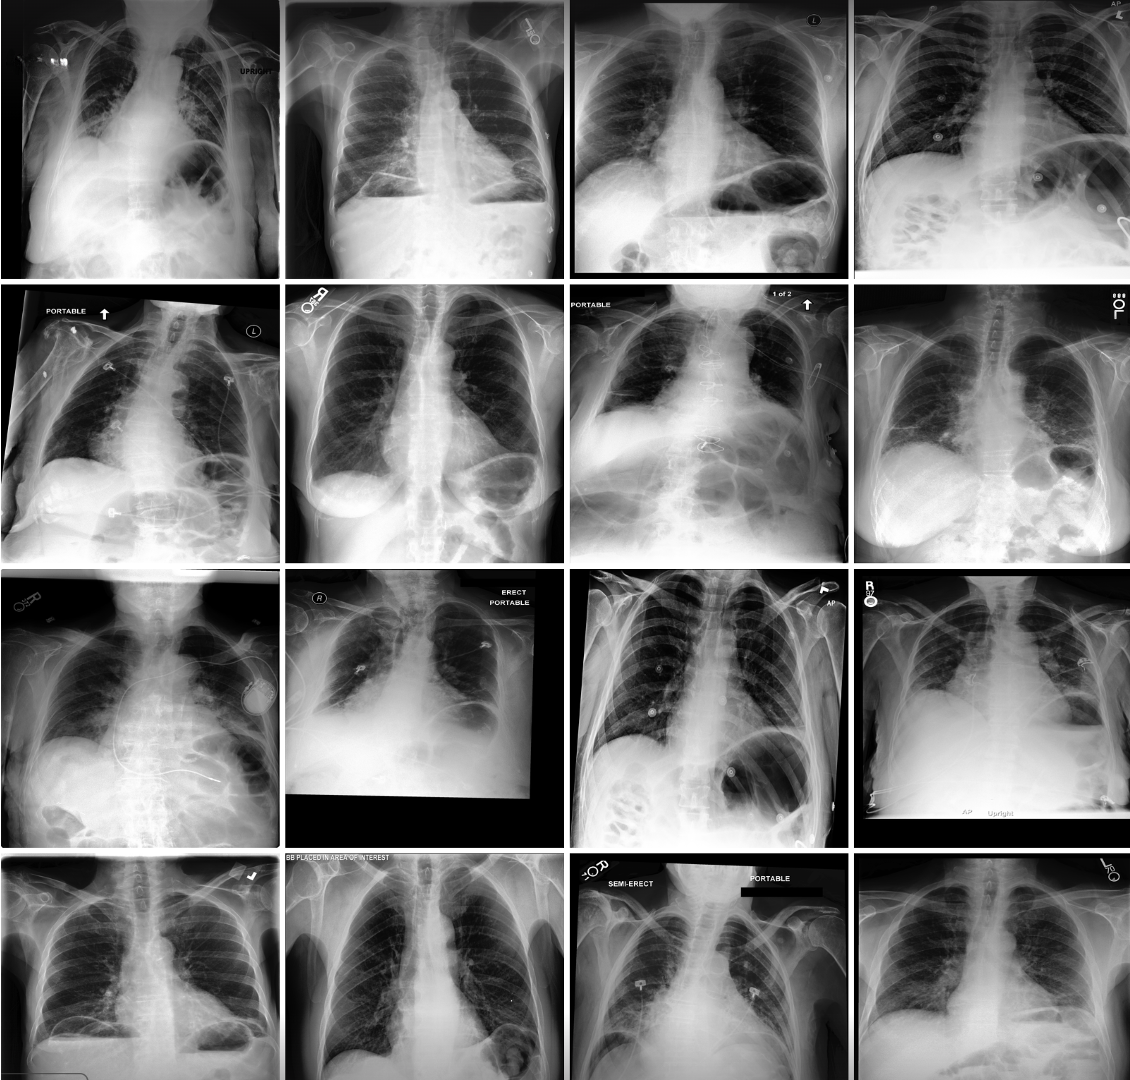

Refer to caption

Figure 3: SAE-Rad accurately captures features reported by human radiologists and more. Above, we showcase a side-by-side comparison between a ground-truth radiology report and one generated by SAE-Rad. The model successfully identifies key clinically relevant features. SAE-Rad also identifies additional details, such as a right-sided dialysis catheter, without hallucination (we annotate this feature with green arrows for emphasis). SAE-Rad can also miss features when compared to the reference report.

Figure 2 illustrates randomly selected monosemantic visual features from SAE-Rad. As can be seen, the SAE learns human-interpretable visual concepts despite the homogeneity and relatively small size of the dataset. These include dextroscoliosis of the spine (Fig. 2; feature 1), bilateral opacifications (Fig. 2; feature 2), unilateral pleural effusions (Fig. 2; feature 3), and the presence of instrumentation – in this case a pacemaker (Fig. 2; feature 4). In Fig. 3, we illustrate an example ‘findings’ section for a CXR with a number of pathological findings; SAE-Rad is capable of detecting multiple relevant pathologies for a given image. Like other radiology report generation systems, SAE-Rad can miss findings. However, it can also occasionally describe a relevant finding which is otherwise missing from the reference report – an example relating to the presence of a dialysis catheter is shown in Fig. 3.